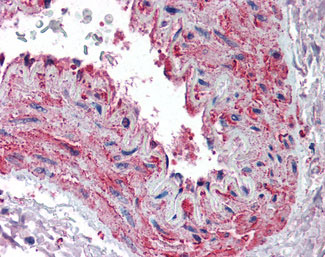

Anti-Beta Actin antibody IHC of human skeletal muscle, vessel. |